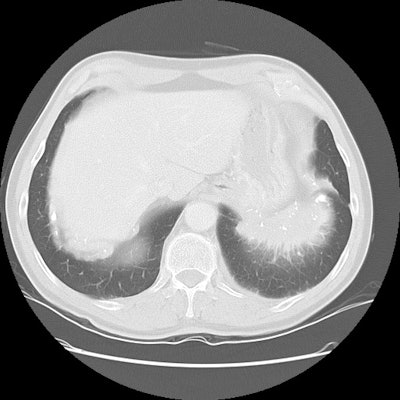

The patient shown on the CT images below presented for evaluation of an enlarging abnormality on CXR. The CT demonstrates exuberant pleural plaque disease along the right diaphragmatic surface. There is a soft tissue mass within the left lower lung that contains a large eccentric calcification. Lung markings radiate into this lesion from the adjacent lung parenchyma and there is distortion of the major fissure. The finding suggested rounded atelectasis, however, the lesion had more aggressive features more inferiorly (see lower CT images). PET images are shown below CT's.